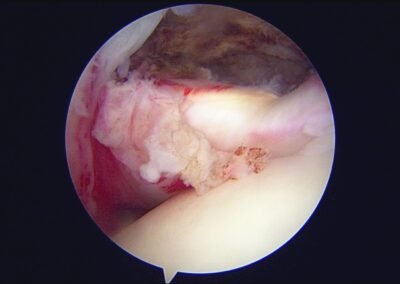

GalleryShoulder rotator cuff repair Meniscus root repair Meniscus repair Bankart repair for recurrent shoulder dislocation ACL reconstruction Machines Instruments